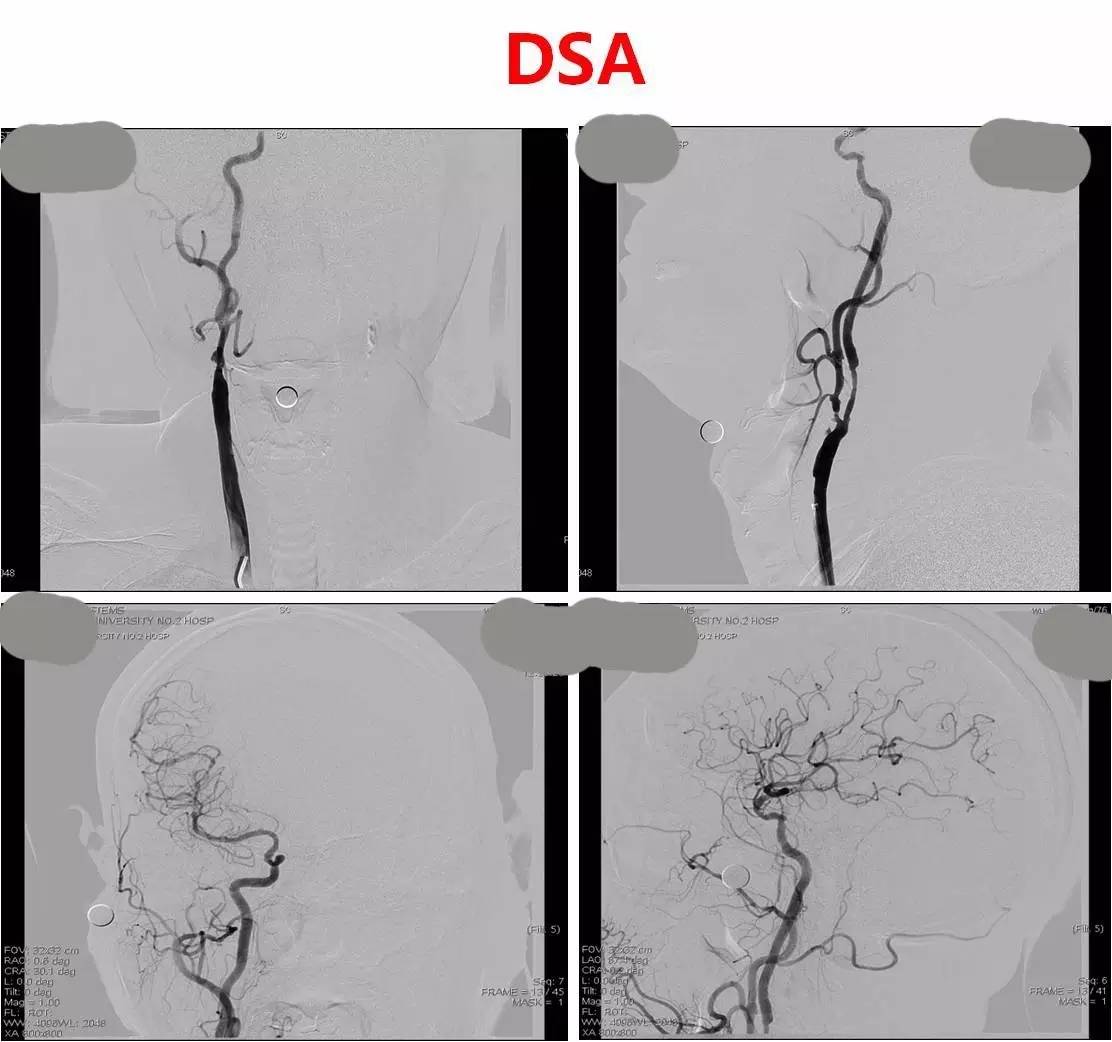

复查DSA,右侧颈内动脉起始部支架定位良好,支架内血流通畅,右侧大脑中动脉显影无异常。

》急诊行DSA+动静脉联合溶栓+左侧颈内动脉狭窄球扩及支架成形术;

》DSA:双侧颈内动脉起始部狭窄,狭窄率约80%,左侧大脑中前动脉显影差继而行超选择左侧颈内动脉动脉溶栓(rt-PA 5mg 推注),远端显影改善,行左侧颈内动脉狭窄球囊扩张及支架成形术。